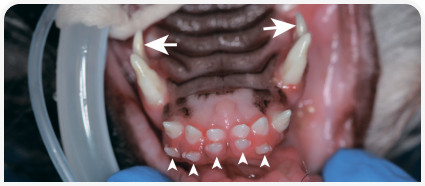

Нарушение прикуса

Нарушение прикуса встречается у многих собак мелких пород. Оно может быть скелетным (неправильное положение челюсти, ее размер или длина), зубным (неправильное положение отдельных зубов) или сочетанным (Рис. 11). У собак брахицефалических пород, к примеру, скелетное нарушение прикуса (относительно мезиальный прикус) закрепляется при разведении. Нарушение прикуса у животного требует ветеринарного лечения только в том случае, если оно приводит к травмированию зубов или мягких тканей. Варианты лечения могут включать удаление причинного зуба, ортодонтическое лечение и подпиливание коронки зуба с последующей эндодонтической терапией или лечением витальной части пульпы.

Рисунок 11. Передние левые зубы у 8-месячной мальтийской болонки с легким скелетным нарушением прикуса («прямой прикус» резцов) и зубным нарушением прикуса (ростральное и язычное смещение левого клыка нижней челюсти [звездочка] привело к его контакту с левым третьим резцом верхней челюсти, в результате вызвав щечное смещение последнего).